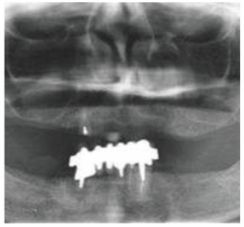

種牙前X光片

種植修復(fù)后X光片

這一位老先生則選擇了All-on-4種植技術(shù),即拔即種,上下頜分別種植4個(gè)植體就完成了全口牙齒修復(fù),費(fèi)用降低了不少,而且創(chuàng)傷小,恢復(fù)快。